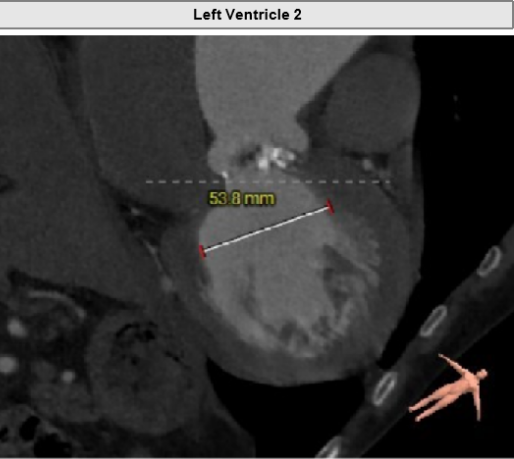

Type1型左右融合二叶式主动脉瓣。

瓣环周长84.7mm,平均周长径27.0mm。

LVOT周长91.7mm,平均周长径 29.2mm。

SOV瓦式窦:36.6mm *35.6mm*39.8mm。

STJ平面周长117.8mm。

升主动脉最大直径66.5mm。

瓣叶重度钙化合并增厚,钙化分布不均,主要集中于左右融合部。

HU419 积分3291mm²。

左冠高度17.9mm,右冠高度13.5mm。

瓣口对应瓣叶稍冗长,术中须注意冠脉风险。

主动脉弓角度与宽度可,心脏水平夹角68°,横位心。

左室腔内径尚可,心室壁稍增厚。